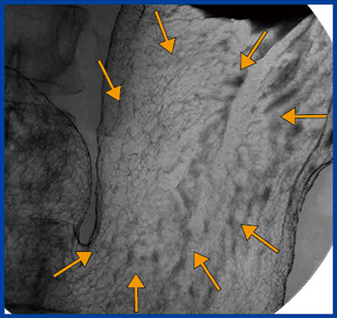

X線検診の追加撮影で,もう1回バリウム造影剤を流すことは,内視鏡検査でインジゴカルミン色素を散布することと同義である。本症例の内視鏡画像でも,インジゴカルミン色素によって前壁の棘状の変化がはっきり見えるようになった(図2)。最近では,NBI(narrow band imaging)や酢酸法なども行われている。

図2 インジゴカルミン色素を散布した内視鏡画像 |